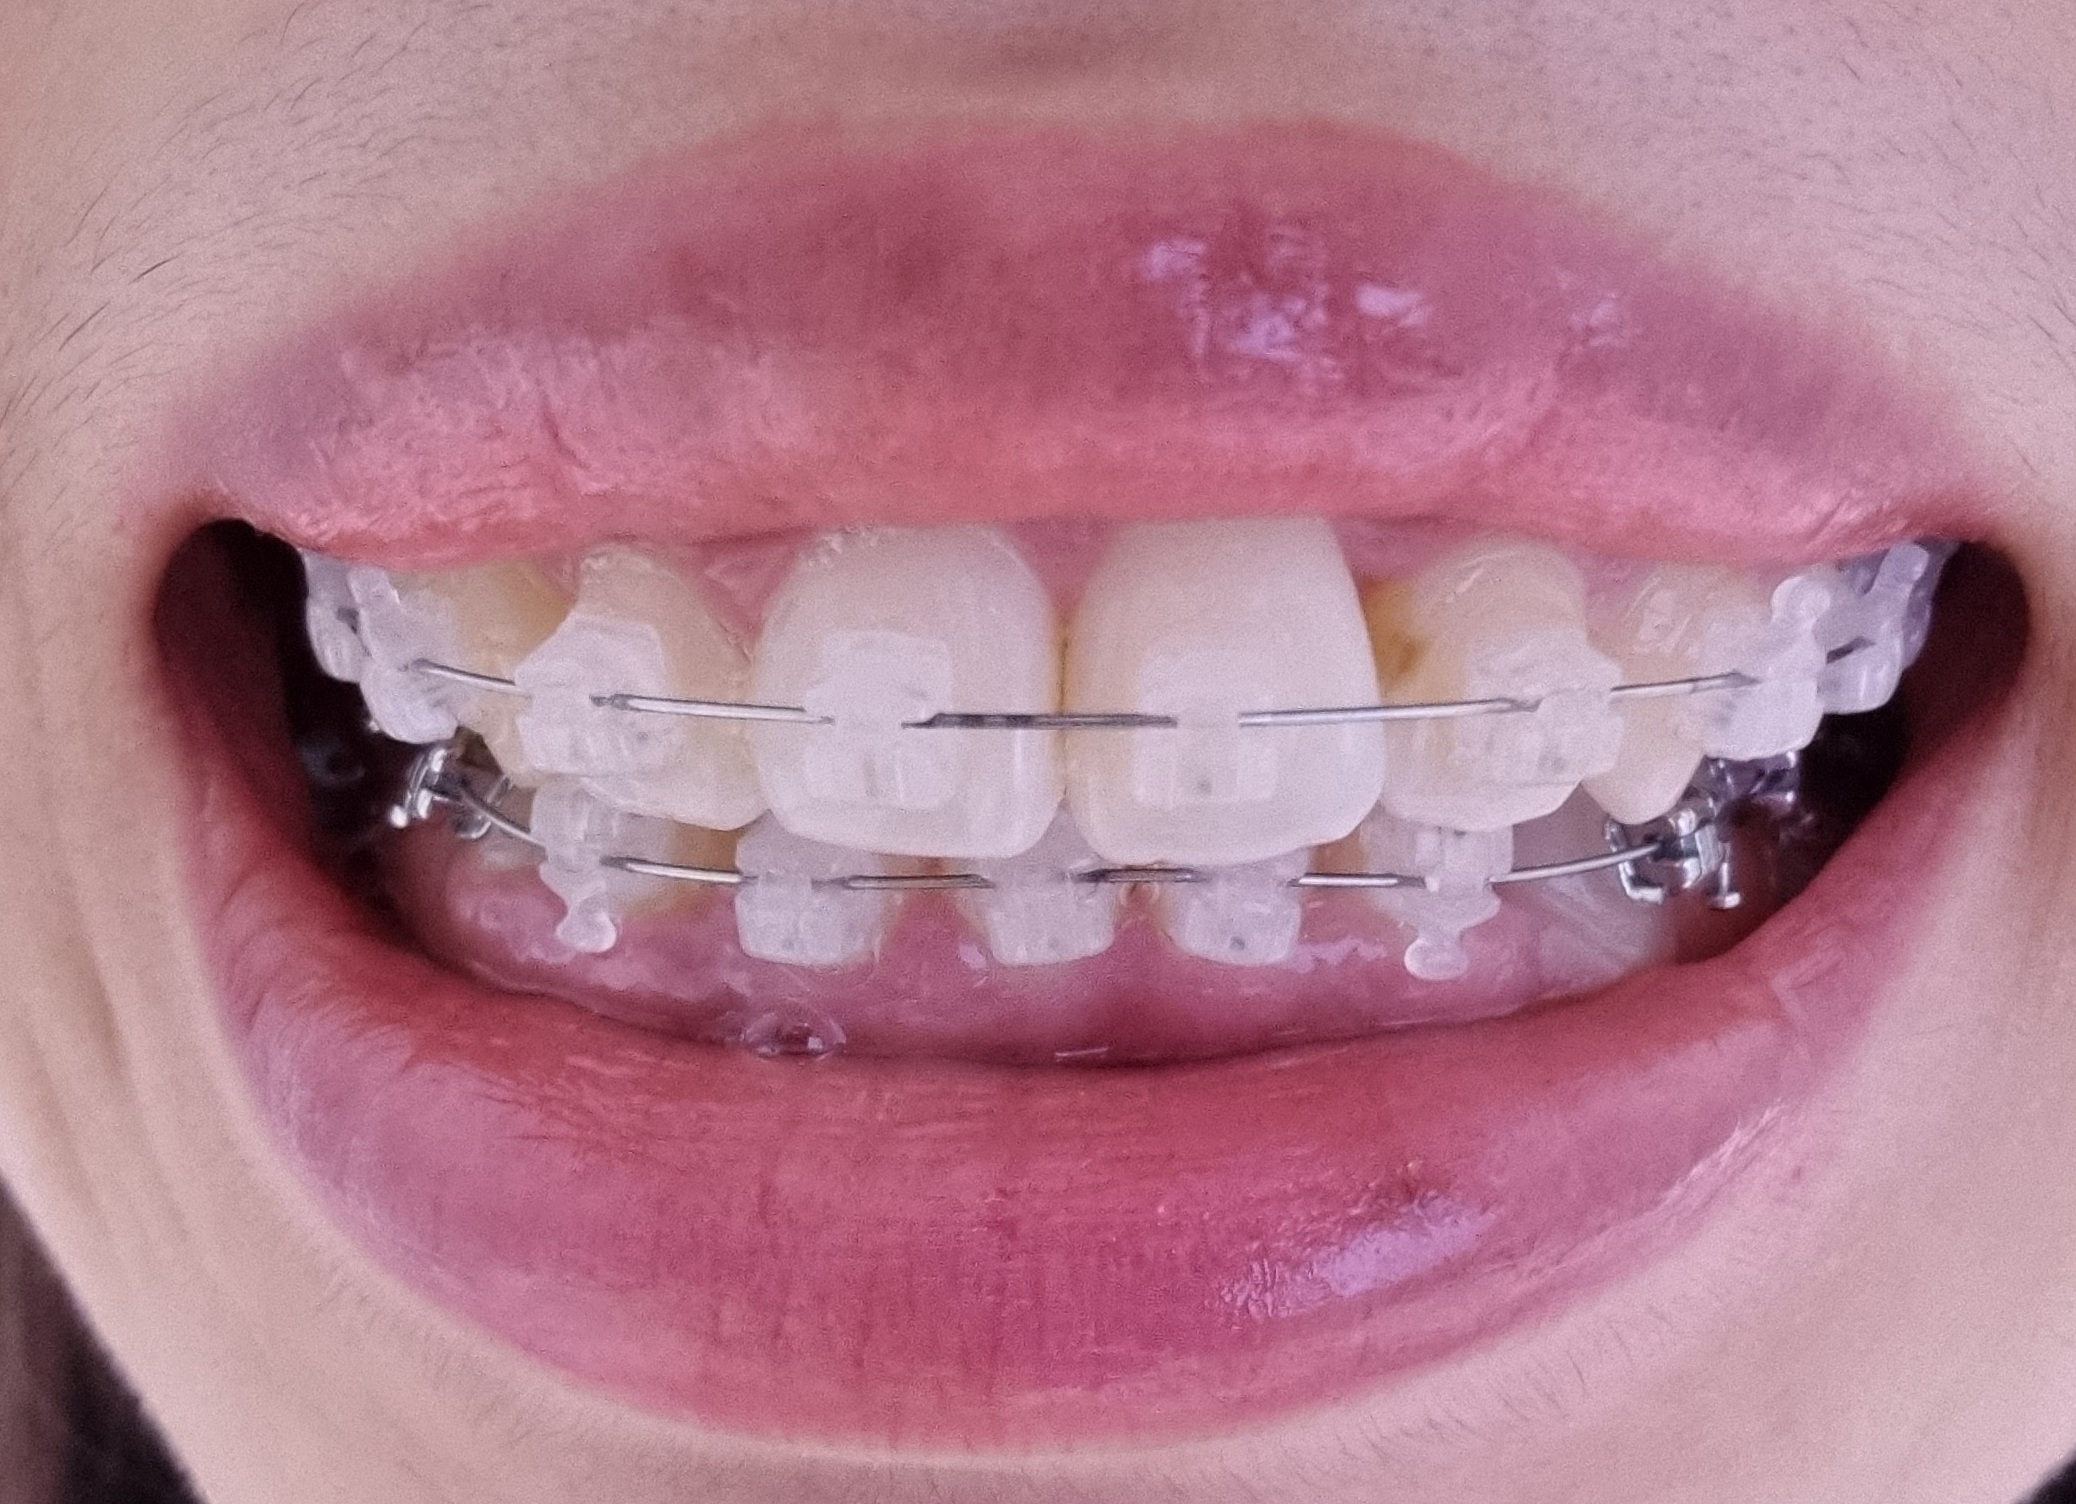

2022-05-02 2022-05-30 D+157 아래랑 위 사진을 비교해 보시면

배열에 있어서 저는 큰 차이는 모르겠습니다.

이번에 윗니 브라켓 위치를 조정해서

자세히 살펴보면 이번 사진(5/30)에서

철사가 일자가 아니고 살짝 구부러져 있는데

한달이 지나면 이게 또 조정이 되어 있겠죠?

이렇게 사진으로 보니까

과개교합의 정도가 개선된 것 같아 보이는데

바이트블럭도 교체했고,

과개교합은 사진 각도 따라서 종종 달라보여서

정확히는 모르겠습니다.

불편한 점이 앞니부분인데,

저번에 붙인 레진을 덜 제거한건지

이번에 붙이면서 레진이 너무 많았던건지는 몰라도

브라켓 위로 삐져나온 레진이 보입니다.

미관상 조금 신경쓰이긴 하는데

나말고는 아무도 모를테니까 그러려니 하려고요